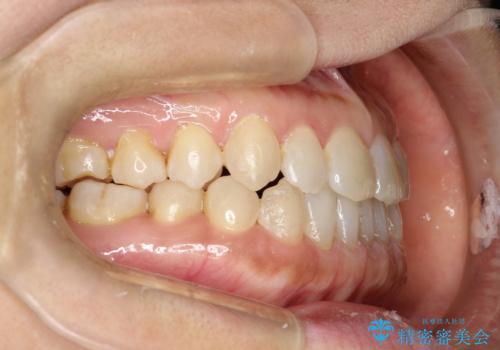

前歯の隙間 インビザラインによる目立たない成人矯正

- 前歯の隙間を気にされて来院されました。

インビザラインにて、目立たずに矯正治療を行うこととしました。

歯と歯の間にある隙間を閉じるのは、インビザラインでもしっかり治療できます。